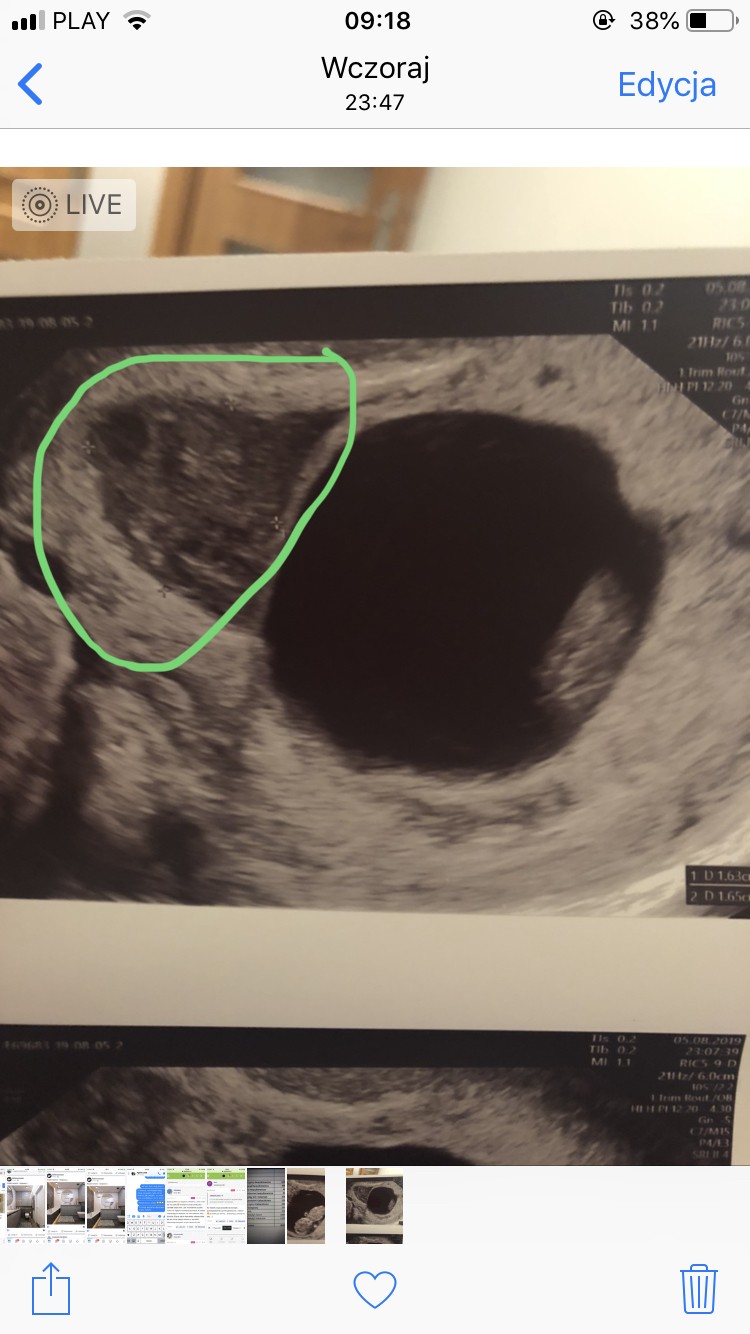

Czyli pracujesz normalnie? Malutki, ale jeśli się zrobił to równie dobrze może się powiększyć, wiec chyba powinnaś leżeć ma zwolnieniu do następnego usg. Zreszta malutki tzn ile? Ja mam 1,6x1,6. Leze plackiem, nie chce ryzykować, bo raz już poroniłam przez krwiaka. Idź na wizytę tak jak piszesz i mam nadzieje, ze już go nie będzie :)

Załączniki

• A278590B-4547-42E1-898F-FD9F5FC12BEC.jpeg

A278590B-4547-42E1-898F-FD9F5FC12BEC.jpeg

133,6 KB · Wyświetleń: 108